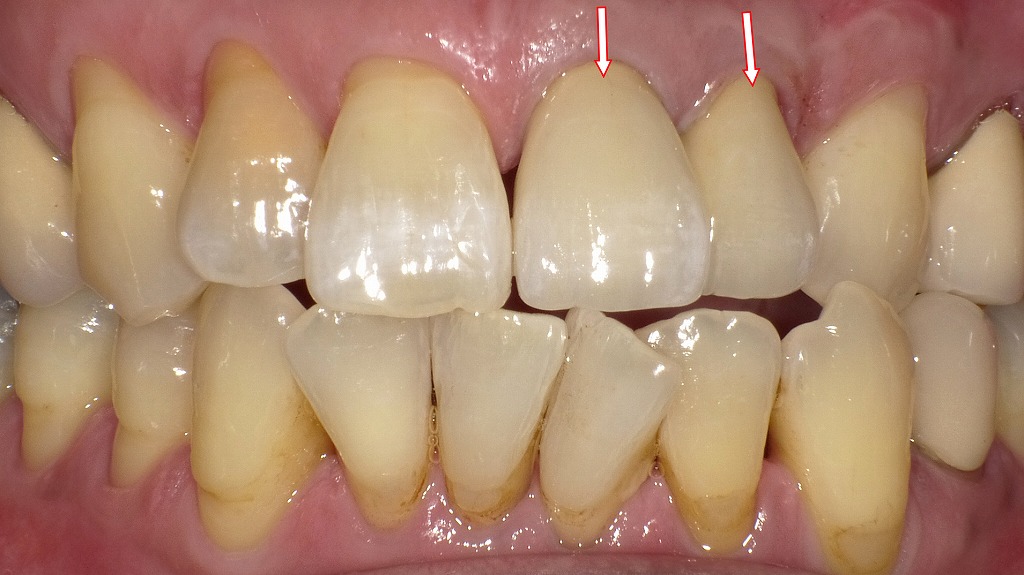

オールセラミッククラウンを装着

この画像は、上顎前歯にオールセラミッククラウンを装着した状態を示しています。赤い矢印の歯が治療対象です。以下に詳しく解説します。

🦷 写真の概要

- 赤い矢印の部分:オールセラミッククラウン

- 以前に神経を失った歯やメタルコアを装着していた歯に、最終的なオールセラミッククラウンが装着されています。

- 天然歯のような透明感と艶があり、周囲の歯と自然に調和しています。

- 金属を一切使用していないため、歯肉の境目も自然で、金属色の影響がありません。

- 歯肉との境界(マージン部)

- 歯と歯肉の境目が滑らかで、炎症や黒ずみも見られません。

- これは、セラミックの生体親和性が高く、歯肉に優しい材料であることを示しています。

- 全体の調和

- 周囲の天然歯と色調・形態が統一されており、審美的に非常に自然な仕上がりです。

- 前歯部の明るさも適切で、自然光下でも違和感のない美しい前歯列になっています。

💡 オールセラミッククラウンの特徴

| 特徴 | 内容 |

|---|---|

| 🌿 審美性 | 天然歯のような透明感と光沢。変色しにくく、長期的に美しさを保つ。 |

| 💎 生体親和性 | 金属アレルギーの心配がなく、歯肉とのなじみが良い。 |

| 🦷 強度 | ジルコニアベースなどを使用することで、十分な耐久性を確保。 |

| ✨ メタルフリー | 金属の影響による歯肉の黒ずみや透過影が起こらない。 |